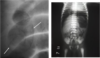

Perforated Peptic Ulcer:

- symptoms

- diagnosis

- treatment

Sx: Acute & SEVERE abdominal pain, peritonitis, hemodynamic instability

Dx: CHEST X-RAY shows FREE GAS UNDER DIAPHRAGM

Tx: resuscitation & surgery